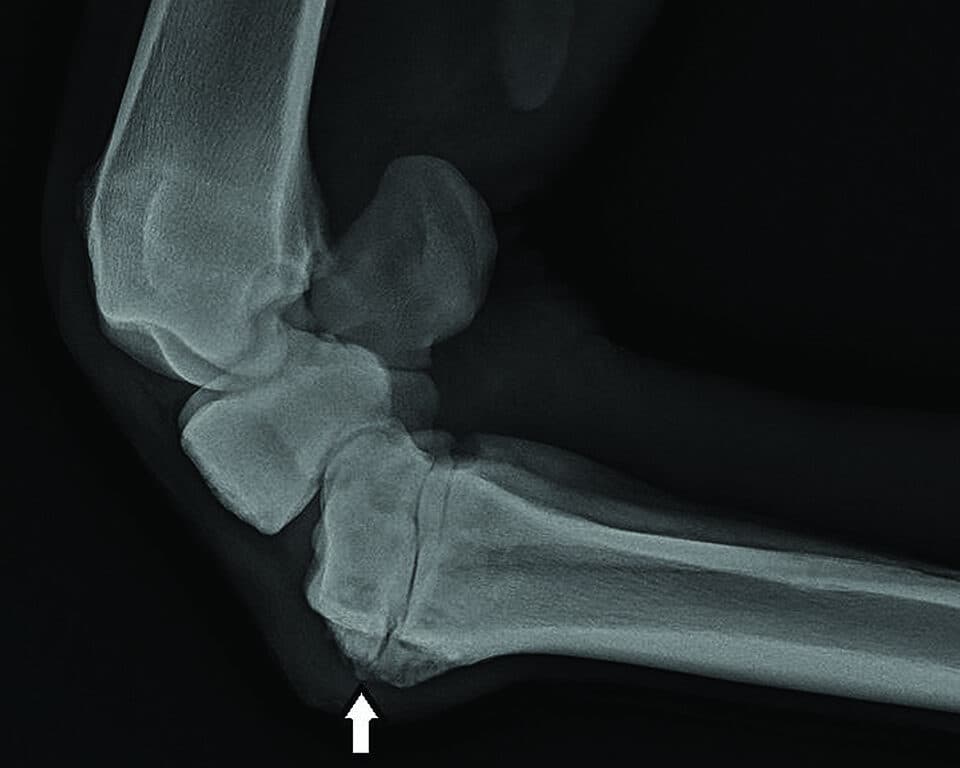

Taking x-rays of the hock. USEA Photo.